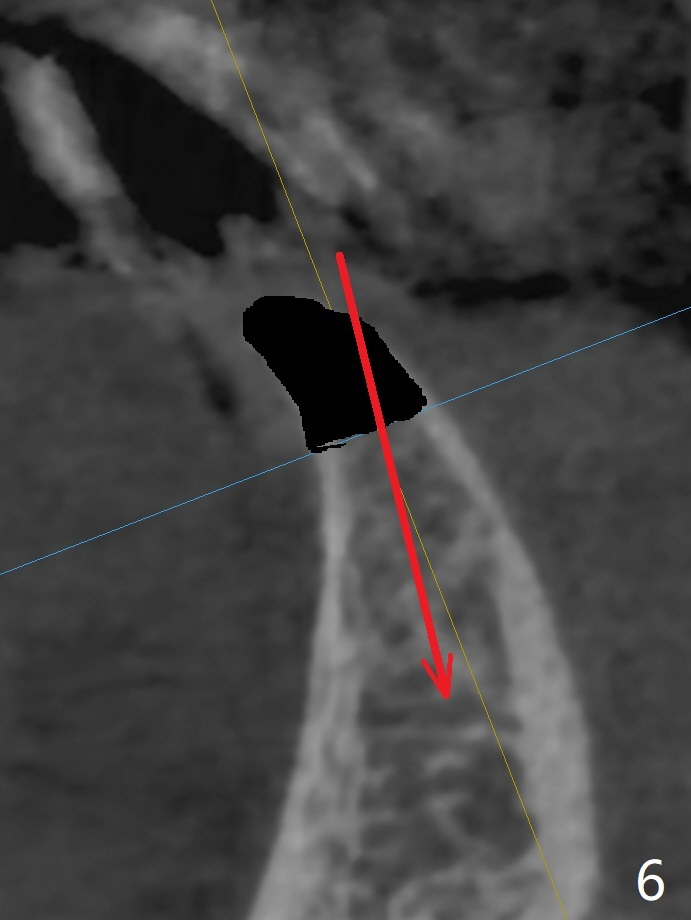

可以重做下颌7个连体牙冠,连接所有牙冠,中缝不再出现,但是费用高,口腔卫生不容易维持。简易办法是种植一个连体植体(1 -piece implant, 2.5x12(4) mm (直径,长度(袖),图二,图三(冠状截面))。 切口暴露狭窄牙槽嵴(图四),截除牙槽顶(图五黑色),然后在平坦骨面开始钻洞(图六红色箭头)。植体尽量种深点防止螺纹暴露,后期骨质密度容易增加。第一个钻头1.5x10毫米,拍摄根尖片,如果方位好,使用2x12mm, 2.5x6 mm钻头,或者2.5mm tap,植体植入。如果方位不好,纠正后,一定要有根尖片证实,才能用下一个钻头。牙槽嵴截除处骨质密度~700单位(图七),不是很高,放置植体前不必用同等大小钻头或者tap。